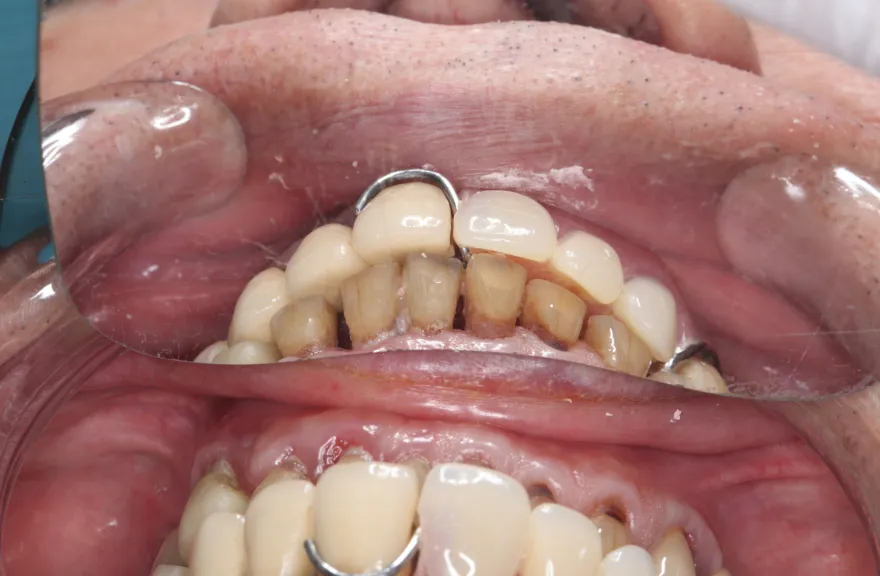

【治療例 3】奥歯が痛い、全体的にみて欲しい 60歳

- 相談内容

-

今まで何回歯を入れてもトラブルが起きるために、奥の歯を入れないまま今日に至る、ということでした。

噛み合わせ・骨格を読み解き、今後の人生でトラブルが起きにくいように全体的な治療計画を練りました。 - 治療費用・方針

骨格の前後的な差がある方でした。術前のレントゲンより、上下で歯牙の損傷に明らかな差があるのがみてとれます。

上の歯がないところにインプラント治療を行い、上顎は全てインプラントフィクスチャーによる固定性の歯を入れられることも費用的には可能な方でした。

しかし、治療において重要なのは今目の前の歯を見ることではなく、なぜ目の前の歯になったかを考え、未来へ活かすことです。

骨格的な前後差を考慮することなく歯をいれても、装着した人工物は決して長持ちしません。

今回の症例では、敢えて上顎は総義歯形態をとり、骨格的な前後の差を解消するよう工夫しました。

上顎の残っていた歯も、差し歯としては使えずとも、敢えて根だけ残すことによって組織を温存し、義歯の安定に寄与するよう設計しました。

ここまで全体的にしっかり治療しておけば、今後の人生においてトラブルになるようなことにはならないでしょう。 - 治療のリスク